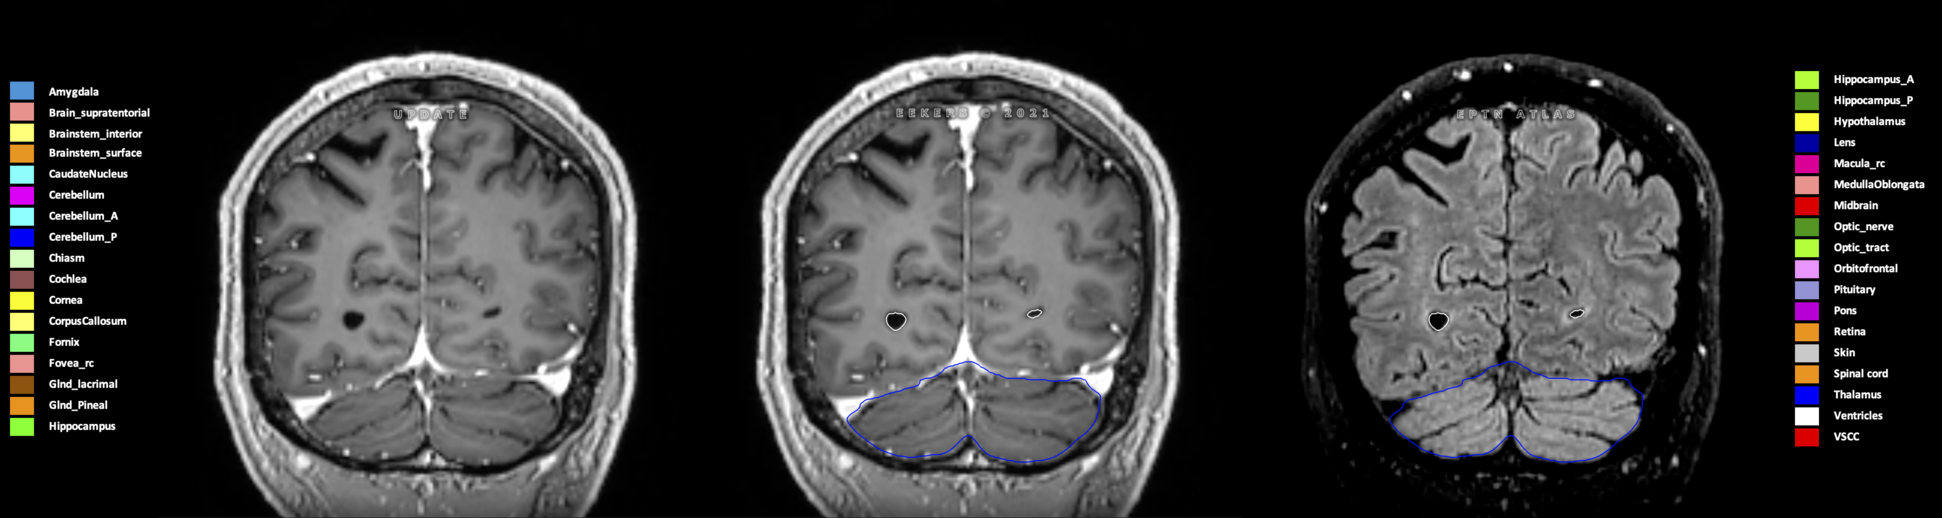

Eekers et al. have published an international neurological atlas for contouring of organs at risk in consensus with the European Particle Therapy Network (EPTN) in 2018 and an update in 2021. The purpose of this consensus atlas is to decrease inter- and intra-observer variability in delineating OARs relevant for neuro-oncology.

Included are all OARs known to be relevant for radiation-induced toxicity in neuro-oncology: brain, brainstem (midbrain, pons, medulla oblongata), chiasm, cerebellum (anterior & posterior), cochlea, cornea, hippocampus (anterior & posterior), hypothalamus, lens, lacrimal gland, optic nerve, pituitary, skin, and vestibular & semicircular canals. To further facilitate research on cognition, vision and radiological changes after irradiation of the brain, potential clinically-relevant OARs are included: amygdala, caudate nucleus, cerebellum (anterior & posterior), corpus callosum, fornix, macula, optic tract, orbitofrontal cortex, periventricular space (PVS), pineal gland, and thalamus.

Three-dimensional delineation of the 25 consensus OARs for neuro-oncology are shown on CT (WW/WL 120/40, 3000/600), 3T MR images, (T1Gd, T2FLAIR 1mm) and 7T MR (MP2RAGE 0.7 mm). All are presented in transversal, sagittal and coronal view.